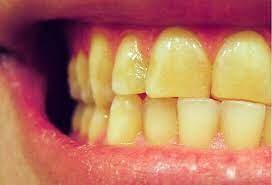

Can Yellow Teeth Be Caused By A Medical Issue?

One of the biggest trends I’ve been seeing online lately is self-care. This means an uptick in skincare, physical therapy and comfort practices like acupuncture and massage, and our favorite for obvious reasons: teeth whitening. We’ve been seeing a ton of UV lights and charcoal pastes being promoted on social media by celebrities and influencers and we think this is great. Taking time to take care of yourself, your teeth included, is a great way to build self-confidence and look your best.

If you’re not the type of person who takes a lot of time in your appearance, or even thinks of this as shallow, you might be wondering if yellowing teeth is a sign of any health concerns, or if it’s simply an aesthetic issue. This depends on the source of the yellowing. Yellowing can be linked to a few different sources, and for the most part, they’re harmless. Here are some reasons your teeth might be yellowing over time.

Aging

One of the downsides to getting older is that your teeth naturally begin to turn more yellow. As part of the aging process, enamel on our teeth naturally wears thin. Dentin, which is the inner layer of your teeth, has a naturally darker appearance and starts showing through your enamel, or the thin, top layer of your teeth. There are ways you can slow enamel thinning, such as avoiding overly sugary or acidic foods and keeping acid reflux under control. However,  it’s natural for some darkening to occur, often giving the appearance of yellow teeth.

Genetics

You might not have known this but teeth yellowing can actually be due to your DNA. In the same way that your parents and ancestry influences your hair, skin and eye color, they can influence the color of your teeth. This is because of the thinness of your enamel. If you naturally have thinner enamel, your darker dentin will start to show, just as we mentioned in the last section.

Chemicals

There are some childhood medications that can affect the yellowing of teeth. This is because some ingested chemicals in those medications can damage your dentin. Tetracycline, an antibiotic that is sometimes used to also treat asthma and allergies can yellow or otherwise discolor teeth. Now that we know this, many doctors know that it’s best to hold off on prescribing these until about age 10, but if you took this or a drug that reacts in a similar way, you might be left with those lasting effects. Chemotherapy and other radiations can also affect this.

Yellowing teeth can be caused by medical reasons, but none of them are especially concerning. However, yellow teeth aren’t very aesthetically pleasing in the eyes of most. As mentioned before, taking care of your teeth is a great way to build self confidence, so even if you’re someone who doesn’t spend much time worrying about your appearance, having your teeth whitenedonce a year can go a long way in building your self esteem.